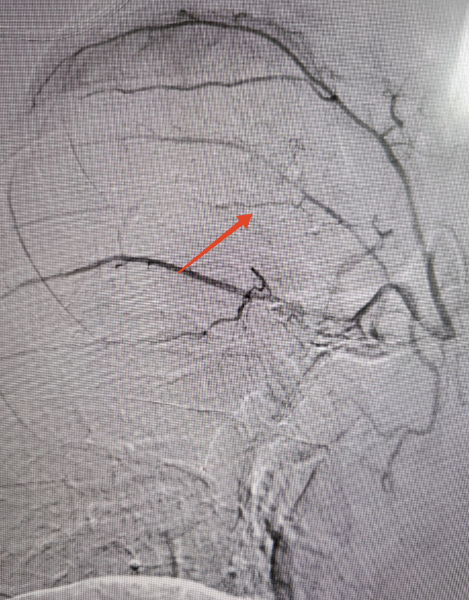

经过多学科讨论,2月4日下午,西安市红会医院介入诊疗中心吴智群教授团队为小伙儿行支气管动脉造影,术中可以看到患者右肺有明显的出血点,给予栓塞后张先生马上不再咯血。术后第1天,张先生精神状态明显好转,术后第3天已经开开心心回家。